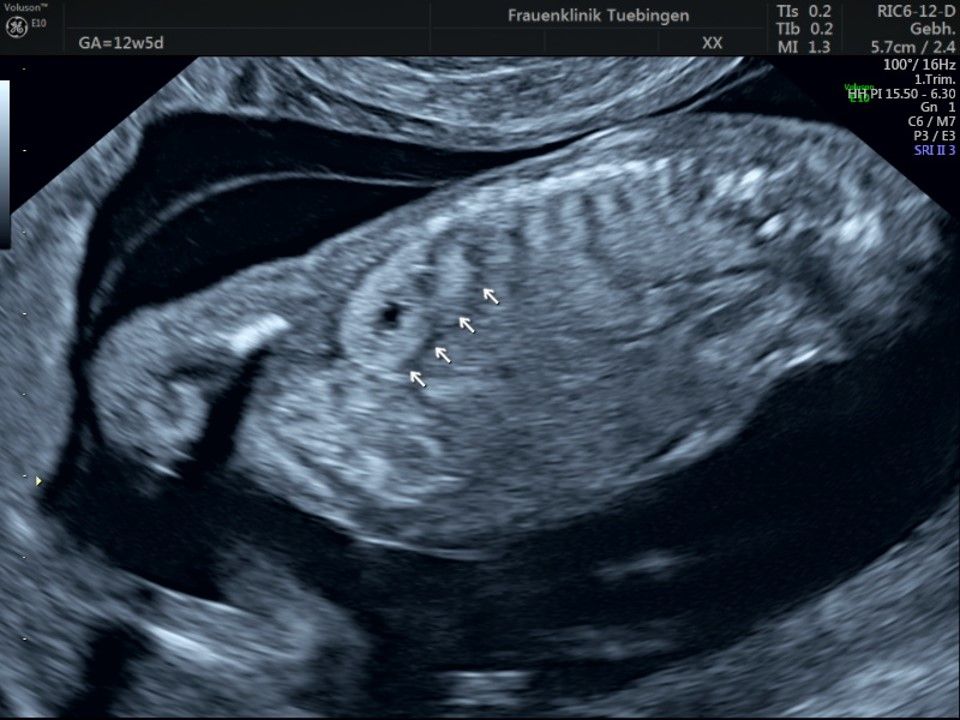

Im Rahmen des Ersttrimester-Screenings untersuchen wir die Organe des Feten mittels Ultraschall. Dabei machen wir auch gerne ein Bild für Sie.

Obwohl der Fet zu diesem Zeitpunkt erst zwischen 5 und 8cm groß ist, lassen sich bereits etwa die Hälfte aller schwerwiegenden Fehlbildungen erkennen bzw. ausschließen. Sollten wir eine Auffälligkeit sehen, werden wir mit Ihnen den Befund und das weitere Vorgehen ausführlich besprechen.

Fetale Anatomie

Das Ergebnis der Ultraschalluntersuchung ist wegweisend. Dabei wird der Fet vermessen, die Organe werden untersucht und die sonographischen Marker zur Risikoberechnung für Chromosomenstörungen werden beurteilt. Das sind: die Nackentransparenzdicke, Nasenbein sowie der Blutfluss in der rechten Herzhälfte und im Ductus venosus, einem Gefäß in der Leber des Feten.